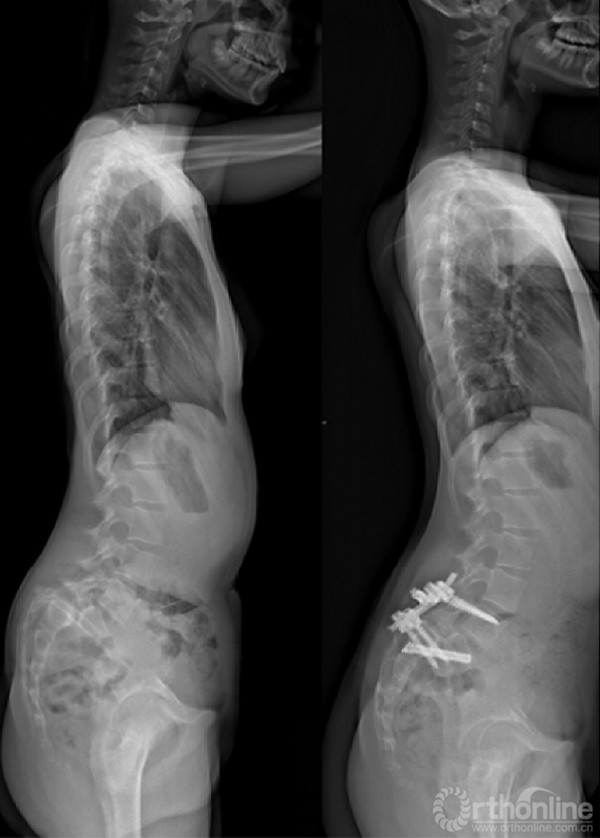

① 对于失平衡不重者,可以采取一期后路部分复位和经骶骨轴向融合方式[4]。

② 明显失平衡者,采取后路复位联合前路支撑重建术式。

① 采取前后联合,骶骨部分截骨、复位和椎间支撑重建手术[8]。

② 我们的病例